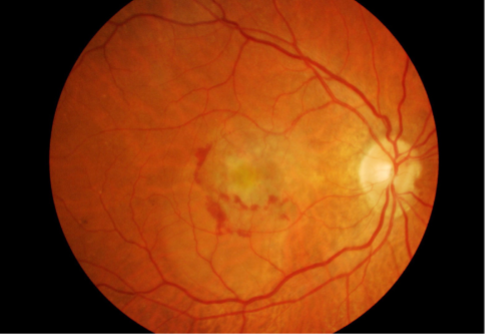

geographic or central areolar RPE atrophy

a form of dry AMD consisting of large areas of GA of the RPE

histologic: the area of GA is associated w/ focal loss of the retinal receptor cells, RPE, & choriocapillaris

5-10% of pts w/ AMD lose central vision as a result of this form of AMD

one or more sharply circumscribed geographic areas of atrophy of the RPE & retinal in the posterior pole

central vision is slow & progressive as the atrophic concentric area enlarges

bilateral, symmetric

20% of these pts will develop CNVM in the 2nd eye

FA shows varying degrees of loss of the choriocapillaris w/in the area of GA

GA

GA

GA

GA

GA